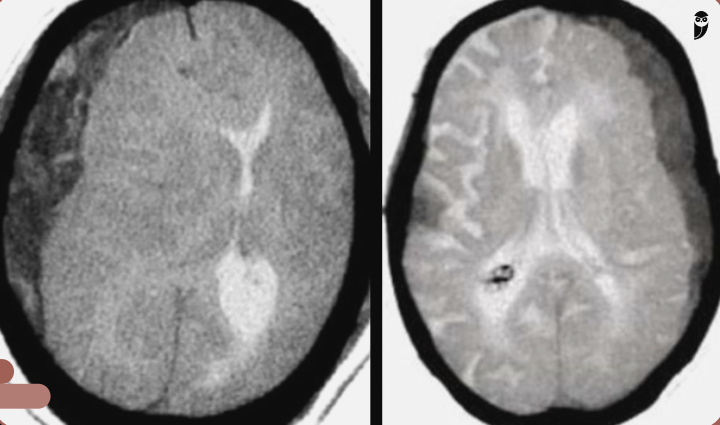

Que tipo de sangramento as imagens a seguir mostram?

Hematoma subdural.